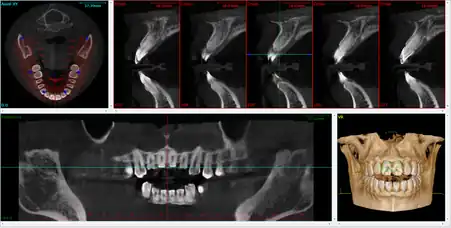

Computed tomography

There is increasing use of CT (computed tomography) scans in dentistry, particularly to plan dental implants;[19] there may be significant levels of radiation and potential risk. Specially designed CBCT (cone beam CT) scanners can be used instead, which produce adequate imaging with a stated tenfold reduction in radiation.[20] Although computed tomography offers high quality images and accuracy,[21] the radiation dose of the scans is higher than the other conventional radiography views, and its use should be justified.[22][23] Controversy surrounds the degree of radiation reduction though as the highest quality cone beam scans use radiation doses not dissimilar to modern conventional CT scans.[24]

Cone beam computed tomography

Cone beam computed tomography (CBCT), also known as digital volume tomography (DVT), is a special type of X-ray technology that generates 3D images. In the recent years, CBCT has been developed specifically for its use in the dental and maxillofacial areas[4] to overcome the limitations of 2D imaging such as buccolingual superimposition.[25] It is becoming the imaging modality of choice in certain clinical scenarios although clinical research justifies its limited use.[4]

Indications of CBCT, according to the SEDENTEXCT (Safety and Efficacy of a New and Emerging Dental X-ray Modality) guidelines include:[4][26]